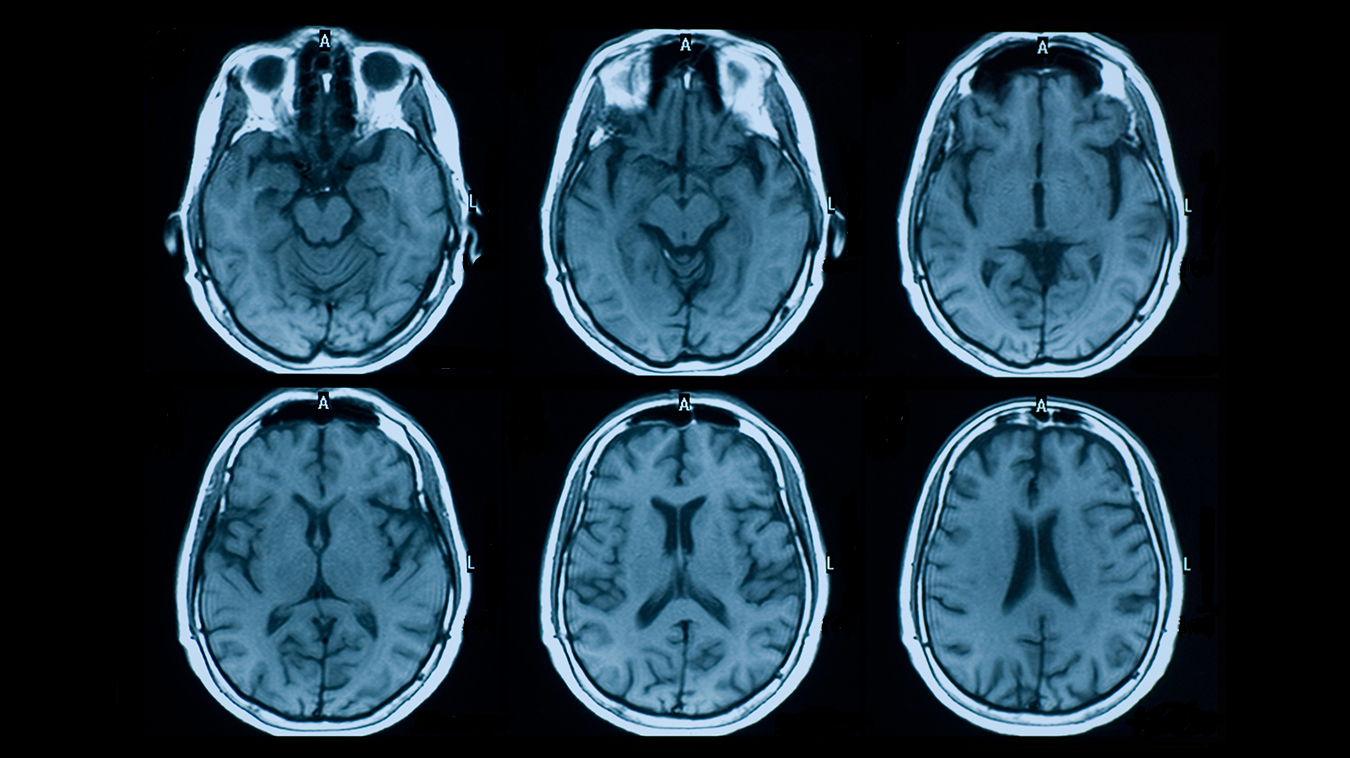

هل هناك فرق في التعافي بين الرجل والمرأة؟ دراسة تكشف قدرة الدماغ على إعادة بناء نفسه بعد الإصابات الرضية

أظهرت دراسة علمية حديثة أن الدماغ يمتلك قدرة مدهشة على استعادة وظائفه بعد التعرض لإصابات قوية، من خلال اعتماد الخلايا العصبية التي لم تتضرر على آلية تعويضية تساعدها على إعادة بناء التواصل العصبي.

وبحسب ورقة بحثية نشرت في مجلة JNeurosci، أجرى فريق من جامعة جونز هوبكنز تجارب على الفئران لدراسة تأثير إصابات الدماغ الرضية على الجهاز البصري، الذي يعتمد على نقل الإشارات من خلايا العين إلى الدماغ لتمكين الرؤية.